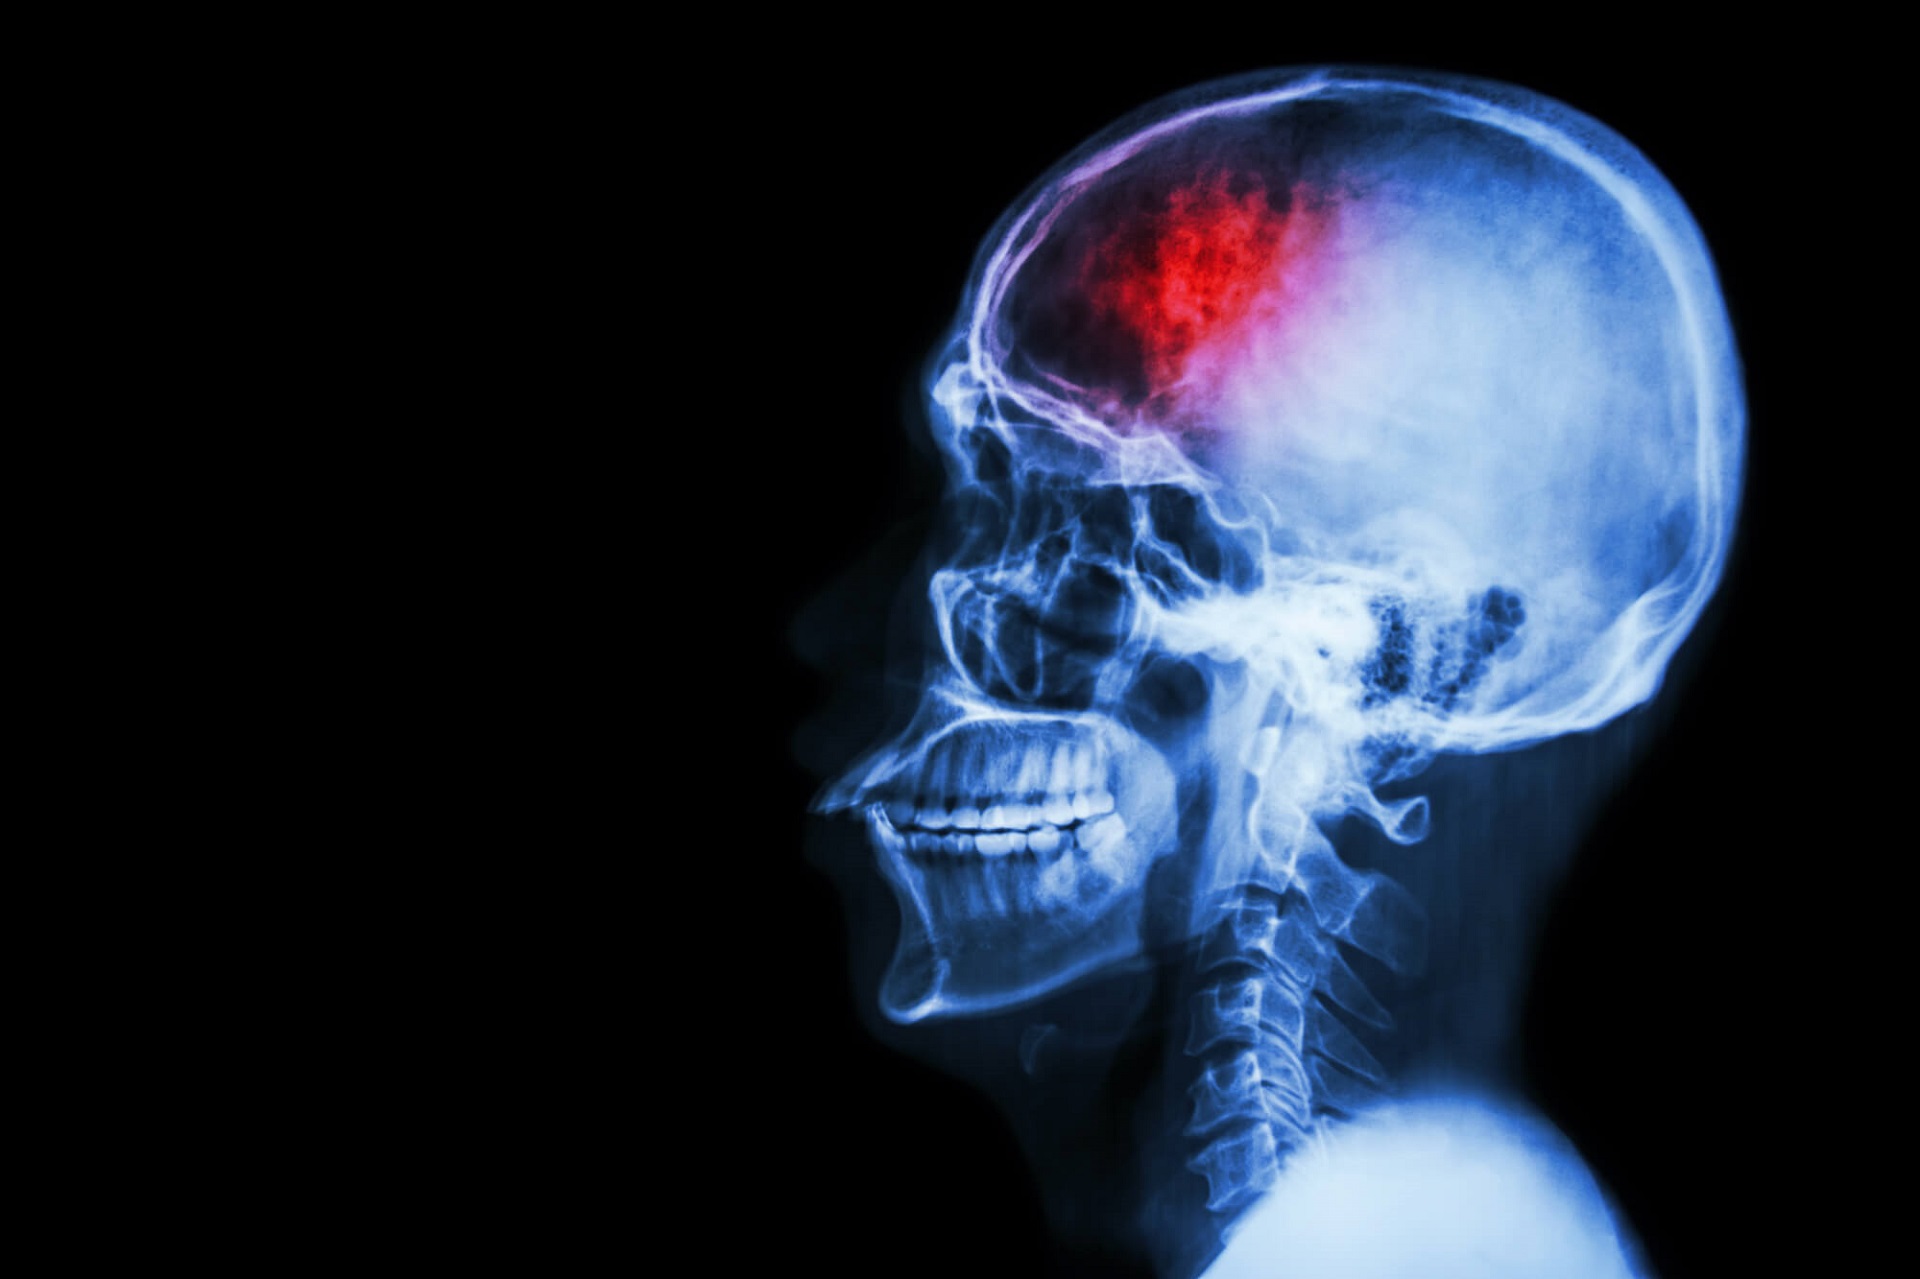

Udar mózgu

Niedokrwienny udar mózgu jest określany jako zawał mózgu i stanowi około 85 proc. wszystkich zachorowań udarowych. Jest on spowodowany zwężeniem lub zamknięciem jednej z tętnic domózgowych lub mózgowych. Niedokrwienny udar mózgu charakteryzuje się wystąpieniem objawów ogniskowych, tj. takich, które są związane z miejsce uszkodzenia mózgu.

Choroba jest drugą co do częstości występowania przyczyną zgonów na świecie i najistotniejszą przyczyną nabytej niepełnosprawności u osób dorosłych. Wyróżnia się dwa rodzaje udaru mózgu – krwotoczny i niedokrwienny, przy czym to udar niedokrwienny jest odpowiedzialny za 4/5 przypadków choroby.